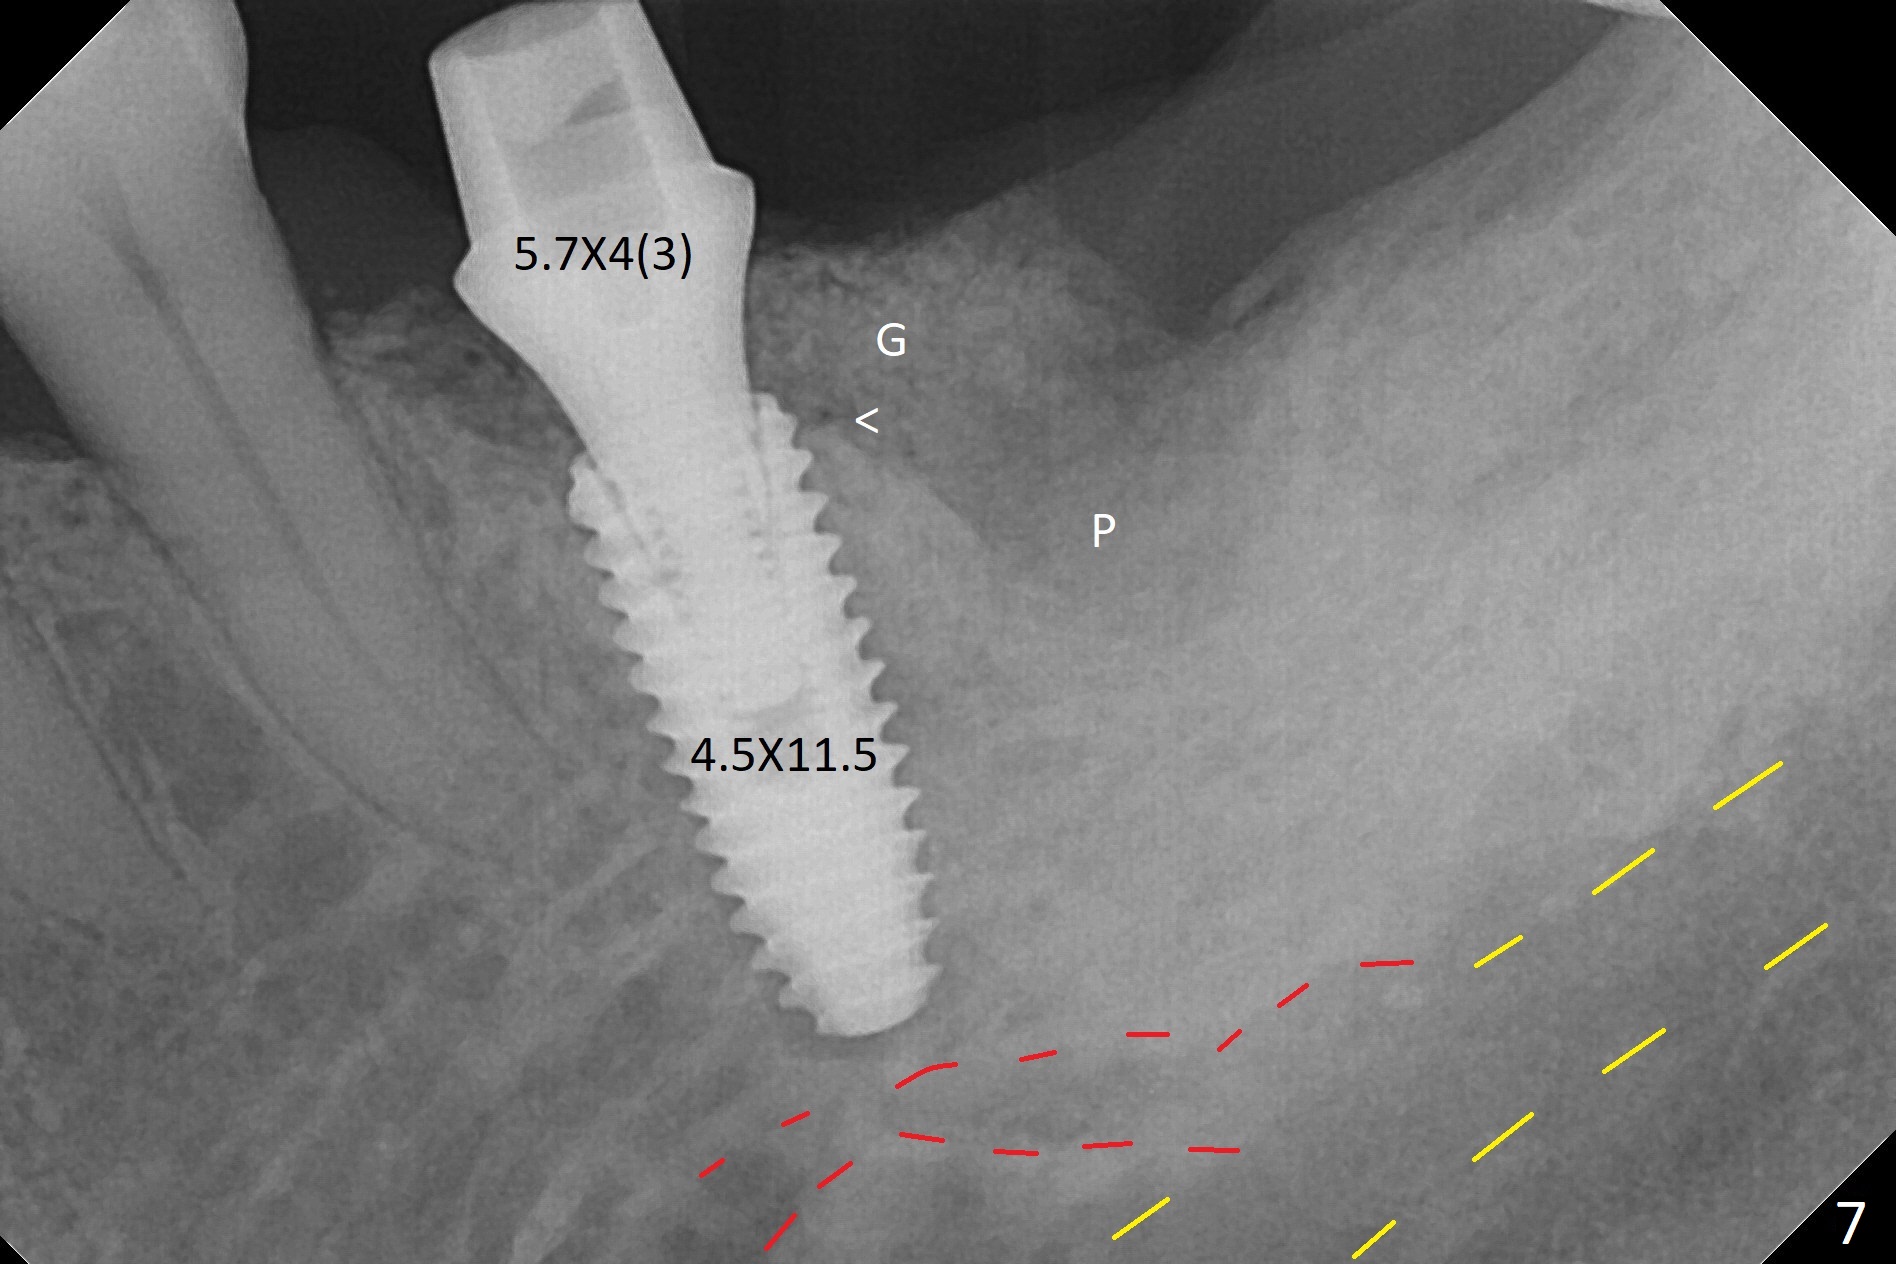

A 68-year-old man returns for extraction of the tooth #19 with distal root periodontal-endodontic lesion (Fig.1 *). After discussion, he agrees immediate implant. A 4.5x11.5 mm implant will be placed in the mesial socket (Fig.2 (red line: superior border of Inferior Alveolar Canal)); the plateau level with the septal crest (<). Osteotomy is initiated in the lingual slope of the mesial socket; the depth is controlled with stopper (Fig.3 S). The implant is placed at the level as expected (Fig.4 <) with insertion torque ~30 Ncm; after placement of 5.7x4(3) mm abutment and Osteogen plug (P) in the apical half of the distal socket, bone graft (G) is placed in the remaining socket gaps, mainly distal and buccal. An immediate provisional is fabricated to keep the graft in place (Fig.5 T). The graft may be lost if the gingival margin recedes in healing. Periodontal dressing is applied for additional security (Fig.6). There is no postop paresthesia. The upper border of the Inferior Alveolar Canal in Fig.3,4 seems to be high. In fact it may be a branch of the Inferior Alveolar Canal (Fig.7 yellow line, as compared to Fig.4). With all of measures taken (including periodontal dressing), the distal bone graft (Fig.8 *) is ~ 2 mm coronal to the crestal bone (red line) 6 months postop. The temporary crown is perforated. The gingival cuff is erythematous. A 6.8x5 mm healing abutment is installed. When the patient returns for impression, a 4.5x5.5(3) mm abutment is fully seated (Fig.9 <). The distal height increases by 4 mm because of immediate implant (support). The mesial papilla remains normal in height and shape immediate post cementation (Fig.10), as related to the mesial socket implant placement without mesial crestal bone loss. The mesial and distal crestal height is maintained 13 months post cementation (Fig.11, weight lifter).